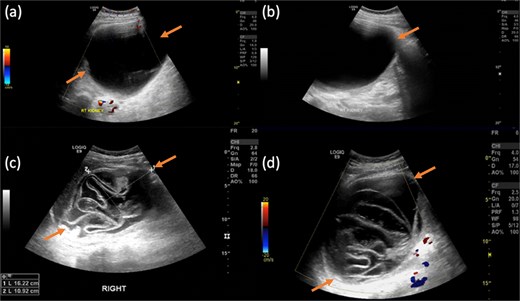

Ultrasound showed a large cystic lesion in the right kidney with internal debris and fluid–fluid levels (Fig. 1). Contrast-enhanced CT confirmed a thick-walled, fluid-filled cyst in the right upper renal pole without septations or calcifications—consistent with recurrent hydatid disease (Fig. 2). Incidentally, a small pelvic cystic lesion was seen adjacent to the rectum and seminal vesicle.

Frontal abdominal radiograph in supine position showing opacity occupying the right upper abdominal region with paucity of bowel loops (a). Followed by contrast enhanced CT abdomen and pelvis with reconstructed images showing a large thick walled non-septated non-calcific right renal cortical cyst (b and c). No right perinephric/pericystic fat stranding or free fluid, preserved tissue planes with surrounding related organs. Incidentally noted small similar looking cystic lesion in the left pelvic region, inseparable from the rectal wall and left seminal vesicle showing no gross fat or calcification (d–f).